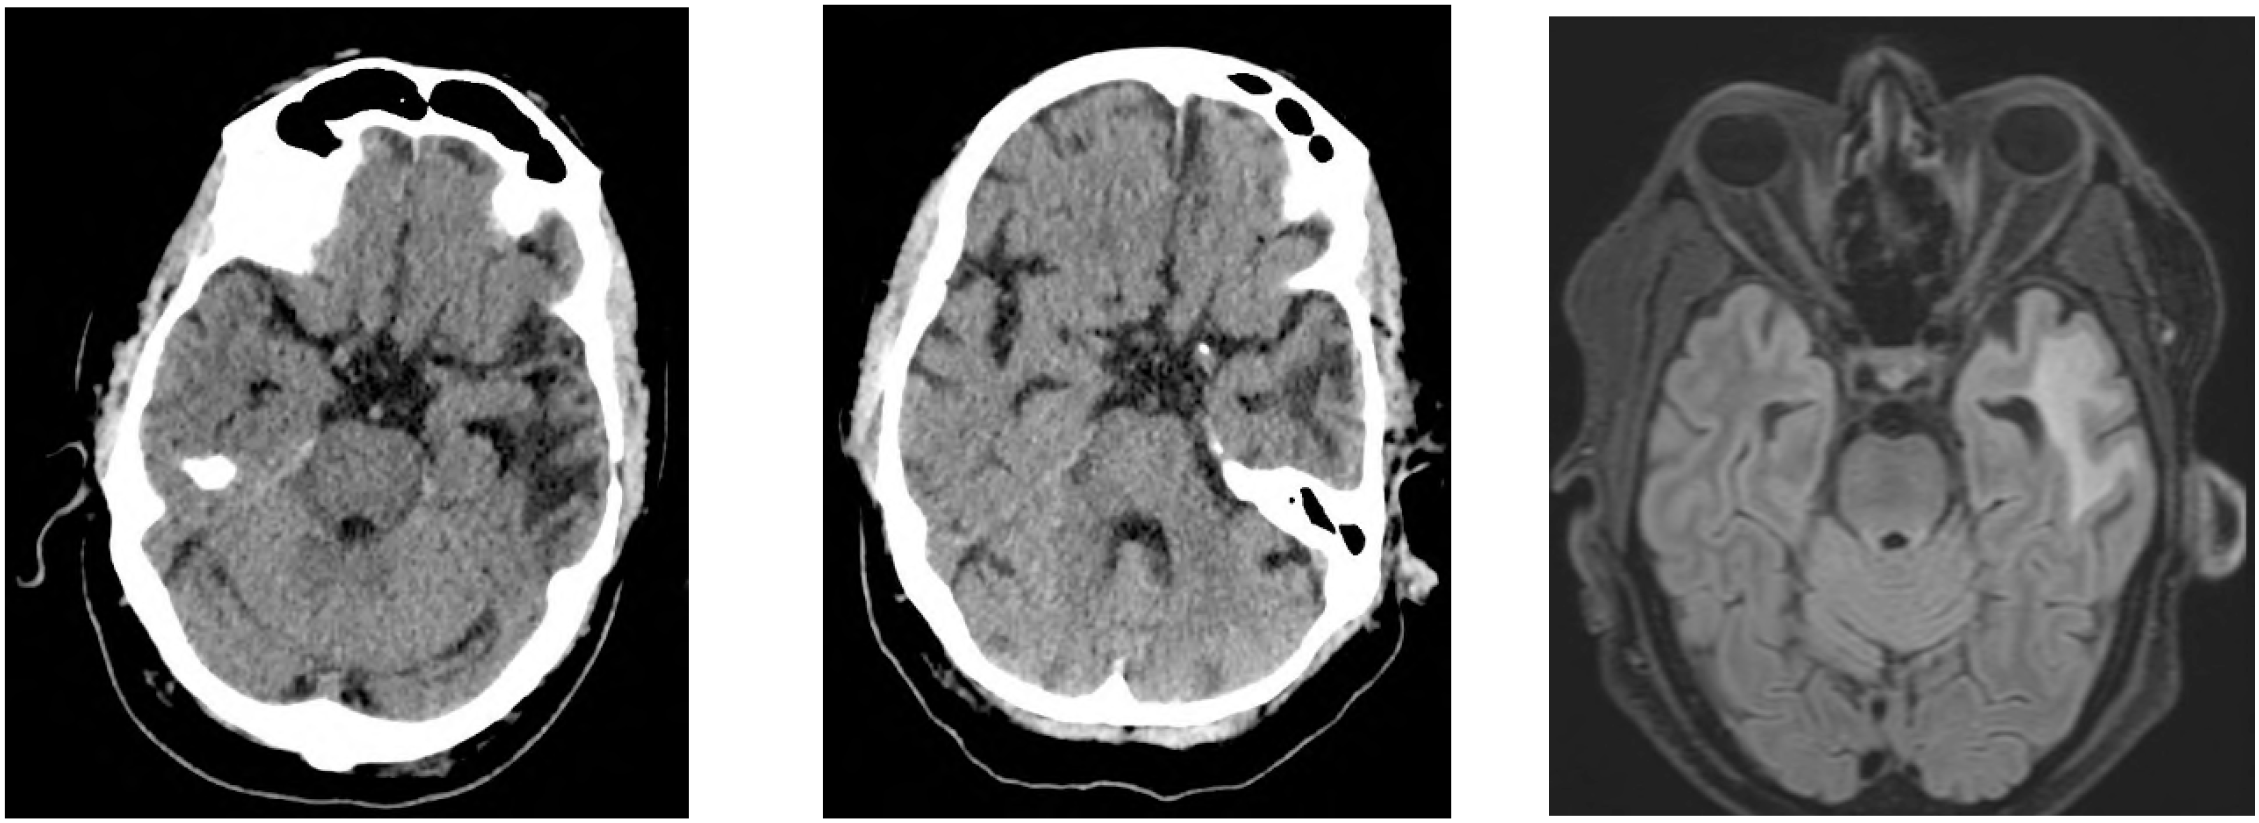

We report a 63-year-old male paƟent with diffuse large B-cell lymphoma (DLBCL) who developed delayed-onset neurotoxicity on day +22 following CD19-directed CAR T-cell therapy with axicabtagene ciloleucel (axi-cel), aŌer an iniƟal episode of CRS and ICANS. The underlying disease had relapsed with secondary central nervous system (CNS) involvement, highlighƟng a high-risk seƫng for neurotoxicity. Unlike classical ICANS, the syndrome featured progressive gait ataxia and hypokineƟc movement disturbances—clinical hallmarks of so-called movement and neurocogniƟve treatment-emergent adverse events (MNTs), a syndrome oŌen referred to as parkinsonism due to characterisƟc features such as bradykinesia, rigidity, tremor, and cogniƟve slowing. To date, such MNTs have only been reported in paƟents receiving BCMA-targeted CAR T-cell products, primarily for mulƟple myeloma. Our report is, to the best of our knowledge, the first documented case of an MNT-like syndrome following CD19-directed CAR T-cell therapy. The paƟent's symptoms evolved subacutely, in the absence of radiographic progression, infecƟon, or lymphoma relapse. Immunophenotyping revealed acƟvated effector-memory CD8⁺ T cells (HLA-DR⁺/CD38⁺/CD28⁻/PD1⁺) in peripheral blood, and predominantly CAR T cells in cerebrospinal fluid. Neurofilament light chain (NfL) levels rose significantly in serum and CSF, indicaƟng neuroaxonal injury. Steroid therapy led to parƟal clinical improvement. Follow-up neuropsychological tesƟng revealed persistent deficits in aƩenƟon and processing speed. This case broadens the known neurotoxicity spectrum of CAR T-cell therapies and underscores the need for heightened clinical vigilance and refined diagnosƟc criteria beyond ICANS, even in CD19-targeted seƫngs.